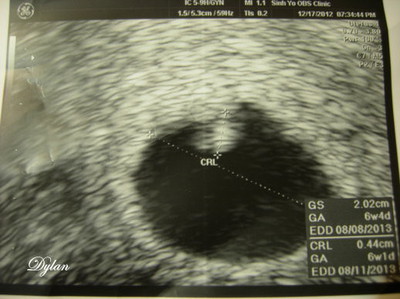

(圖/懷孕週期:6W1D)